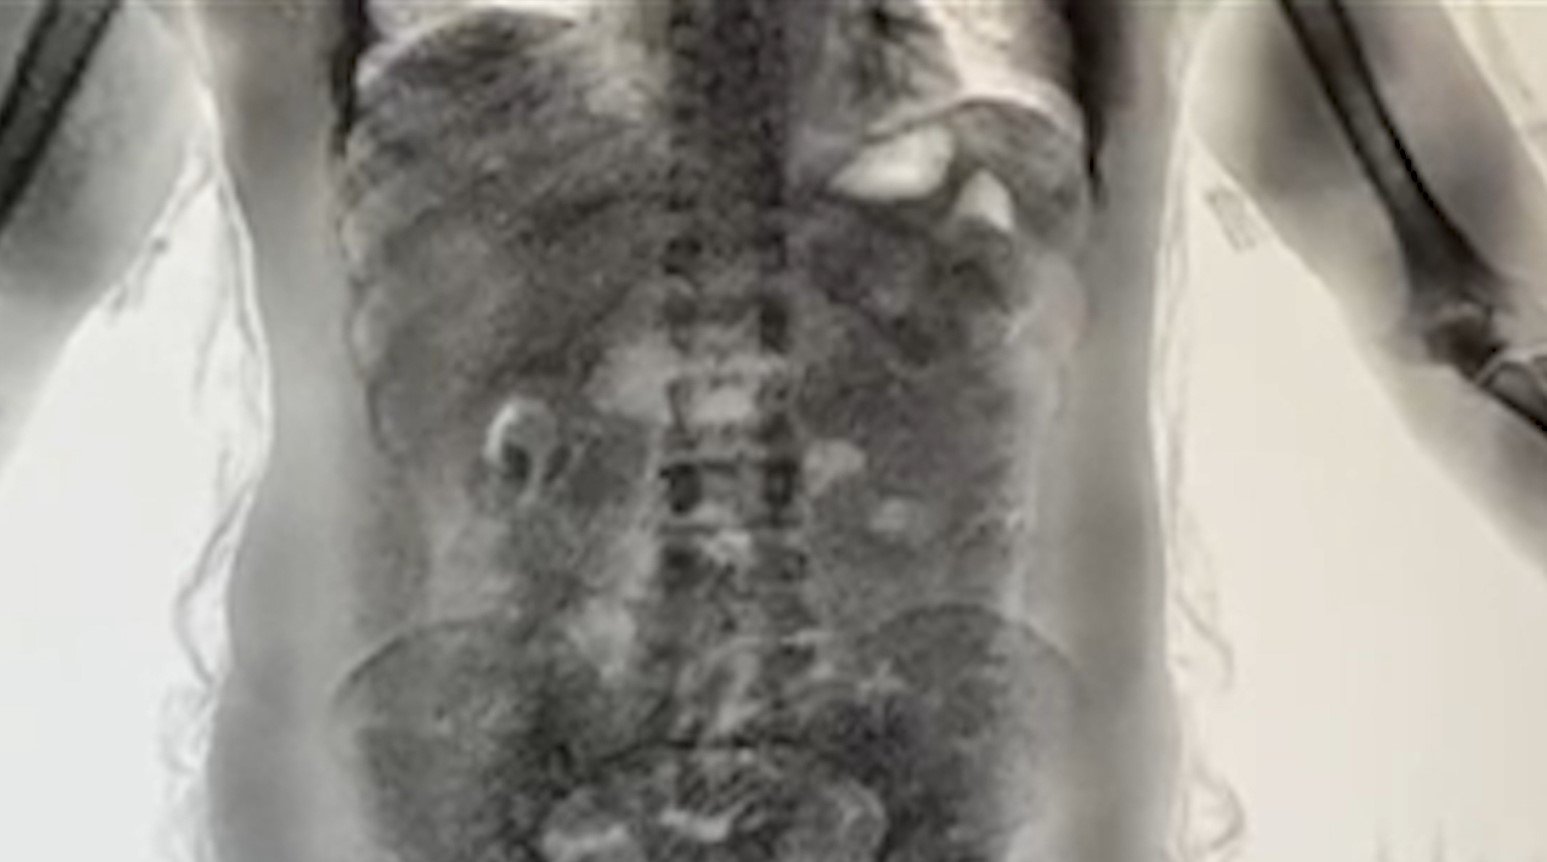

Yutucu Kuryeler Röntgenle Tespit Ediliyor

Yapılan değerlendirmelerde, riskli ülkelerden gelen yolcuların ekipler tarafından yakın takibe alındığı belirtildi. Uçağın kapısından itibaren terminal içerisinde riskli görülen yolcular, ekipler ve güvenlik kameraları tarafından anbean izleniyor. Şüpheli kişiler gümrük ekiplerince durdurulduktan sonra ilk olarak bagajları aranıyor. Yapılan aramalarda herhangi bir bulguya rastlanmaması halinde, hal ve tavırlarından şüphelenilen yolcular ‘yutucu tespit cihazlarının’ bulunduğu bölüme götürülüyor. Burada yapılan röntgen incelemesinde, şüphelilerin mide ve bağırsaklarında uyuşturucu madde bulunduğu tespit ediliyor.

2025 yılında İstanbul Havalimanı’nda yürütülen risk analizleri ve etkin denetimler kapsamında 100’ün üzerinde şüpheli yolcu kontrol edildi. Yapılan incelemeler sonucunda ‘yutucu kurye’ olduğu belirlenen 24 yolcu hakkında adli işlem başlatıldı. Yakalamalarda ağırlıklı olarak kokain cinsi uyuşturucu madde ele geçirilirken, 2025 yılı boyunca ‘yutucu kurye’ yöntemiyle toplam 29,7 kilogram uyuşturucu maddeye el konuldu.